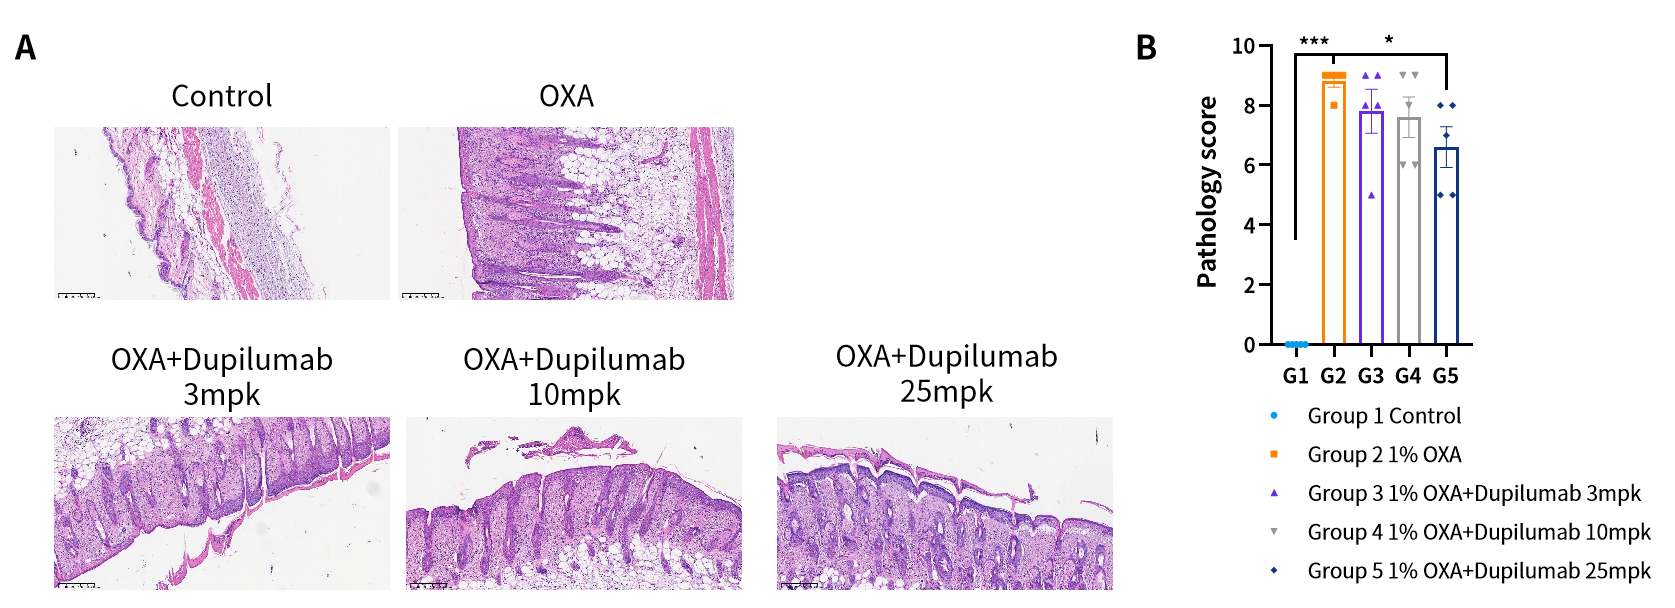

图4. OXA诱导的hIL4/hIL4R小鼠AD模型及Dupilumab药效评价。(A)H&E染色结果图;(B)病理评分。